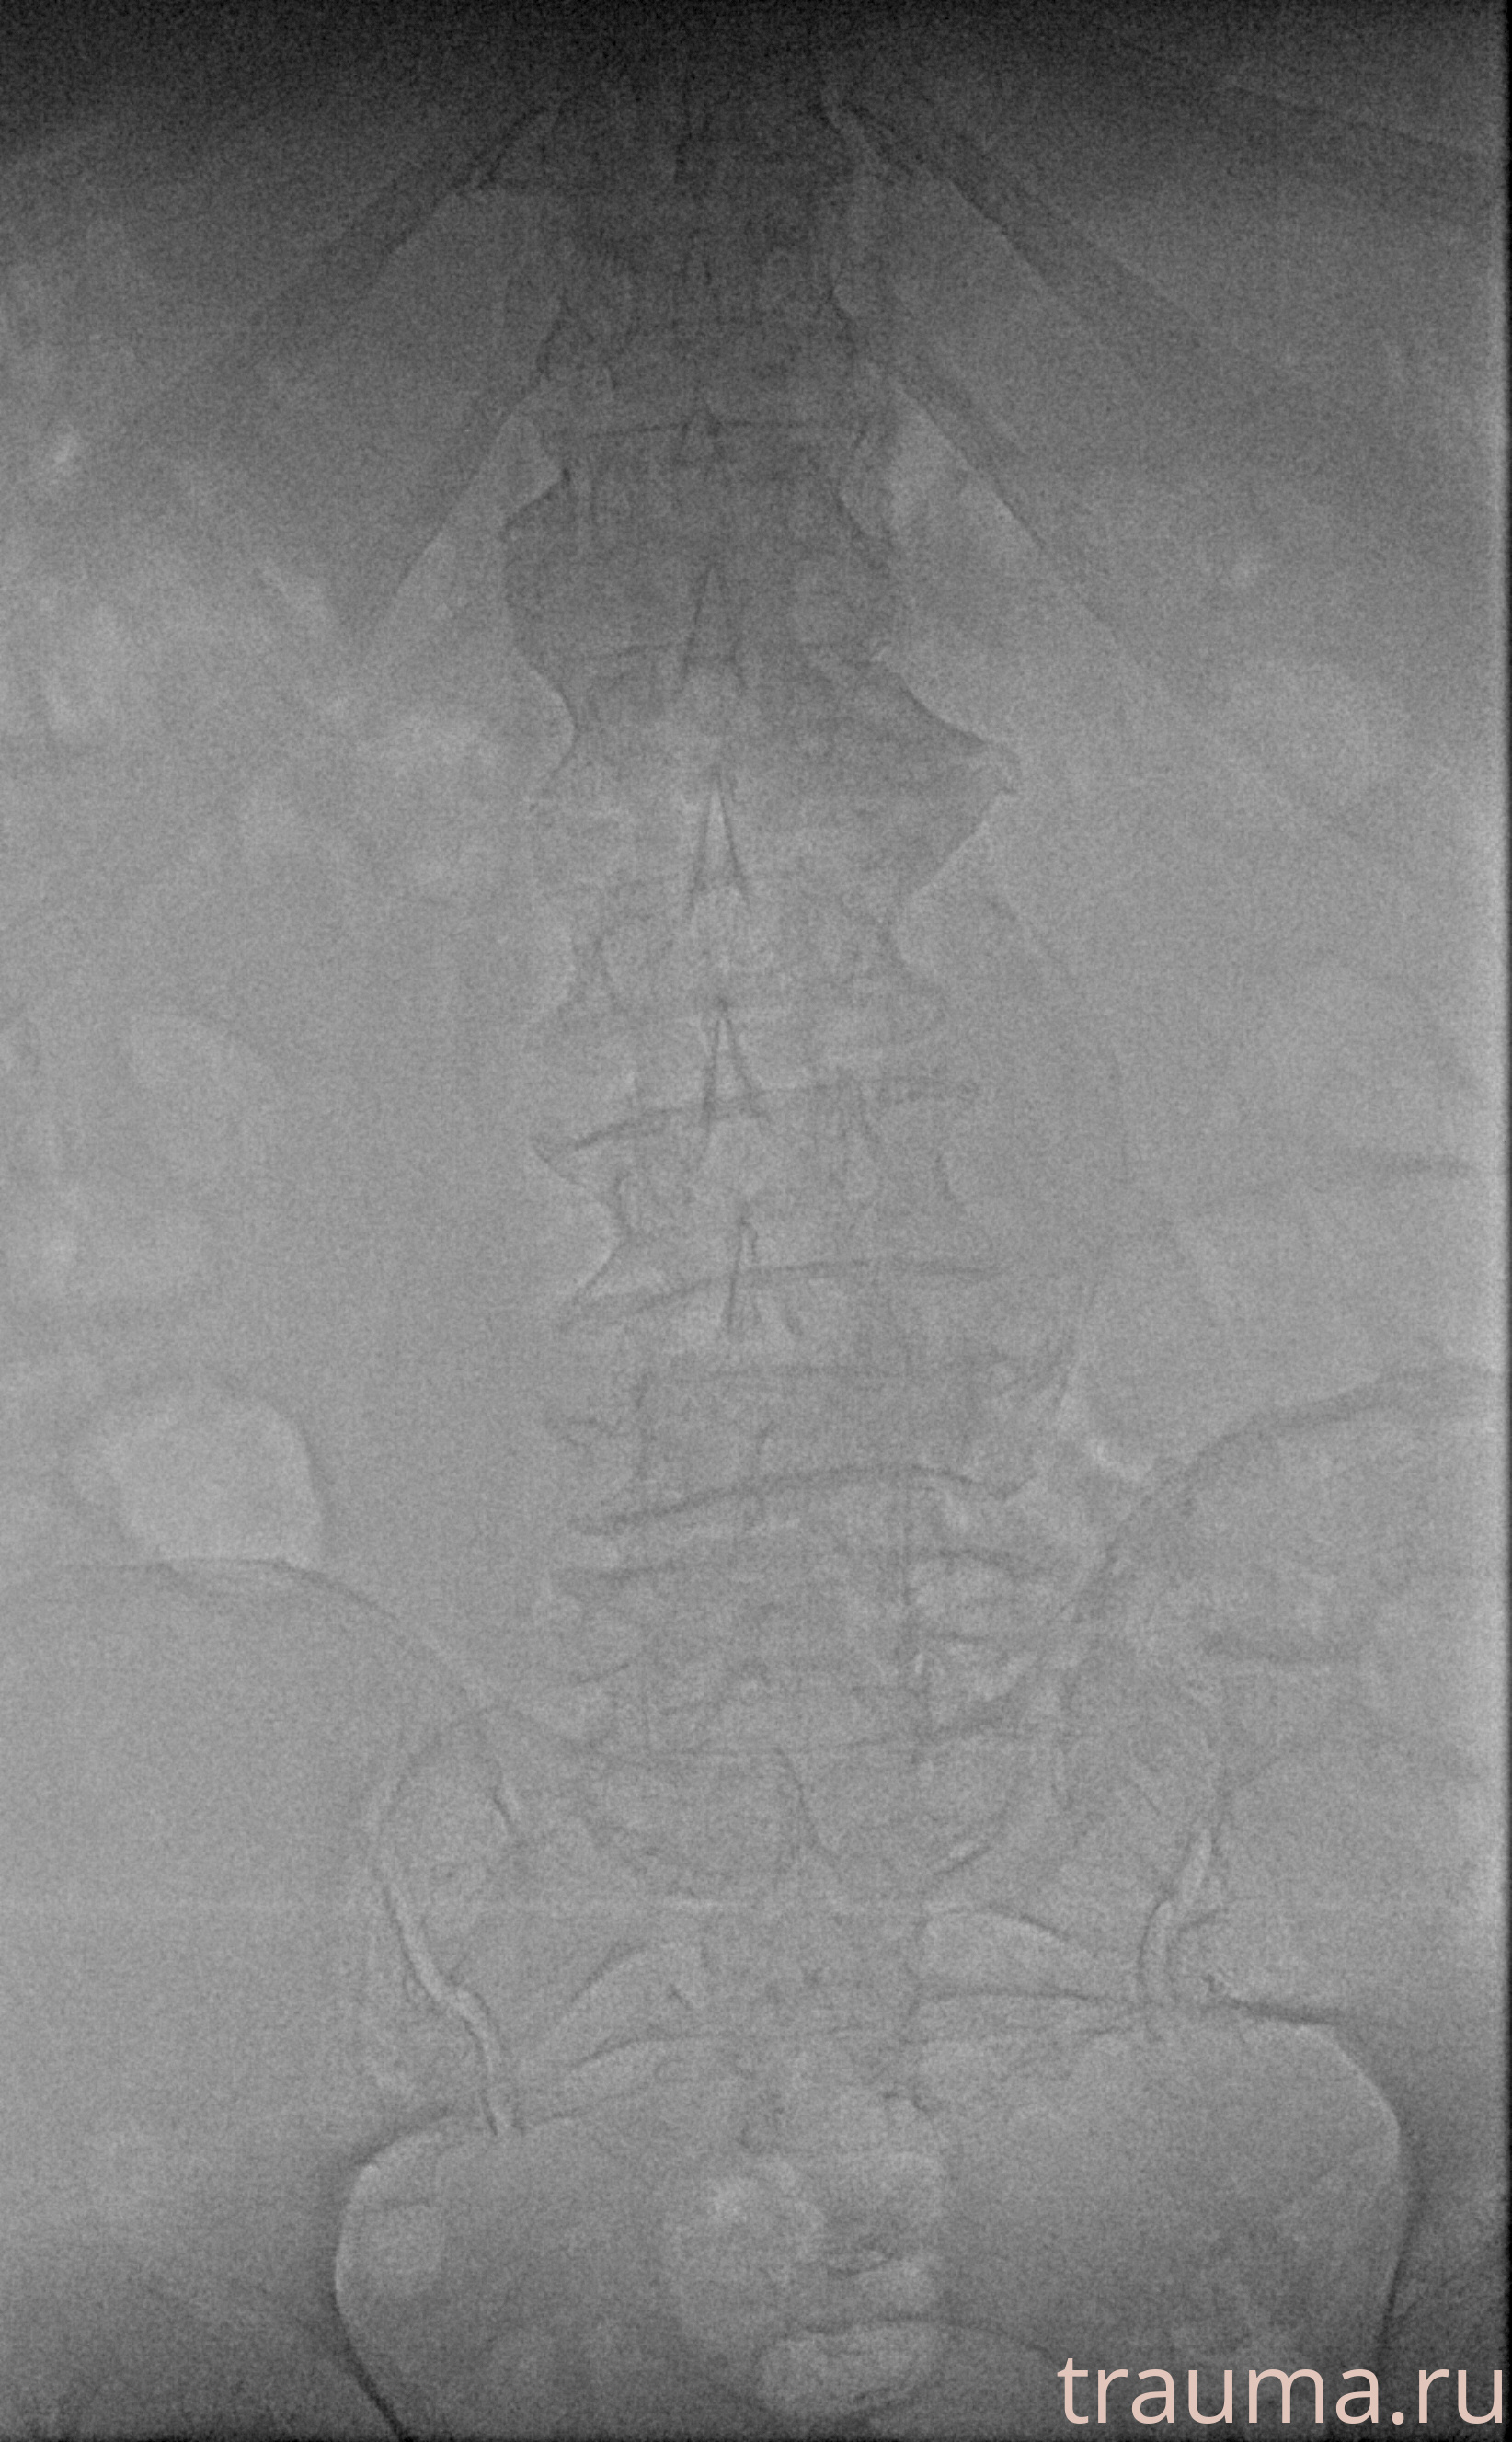

Рентген на дому: по вашему адресу приезжает врач-рентгенолог, травматолог-ортопед с мобильным рентгеновским аппаратом, проводит диагностику травмы или заболевания, делает необходимые рентгенограммы, дает рекомендации по дальнейшему лечению. Получить качественные снимки в домашних условиях возможно благодаря уникальной методике, разработанной МосРентген Центром для института  Склифосовского